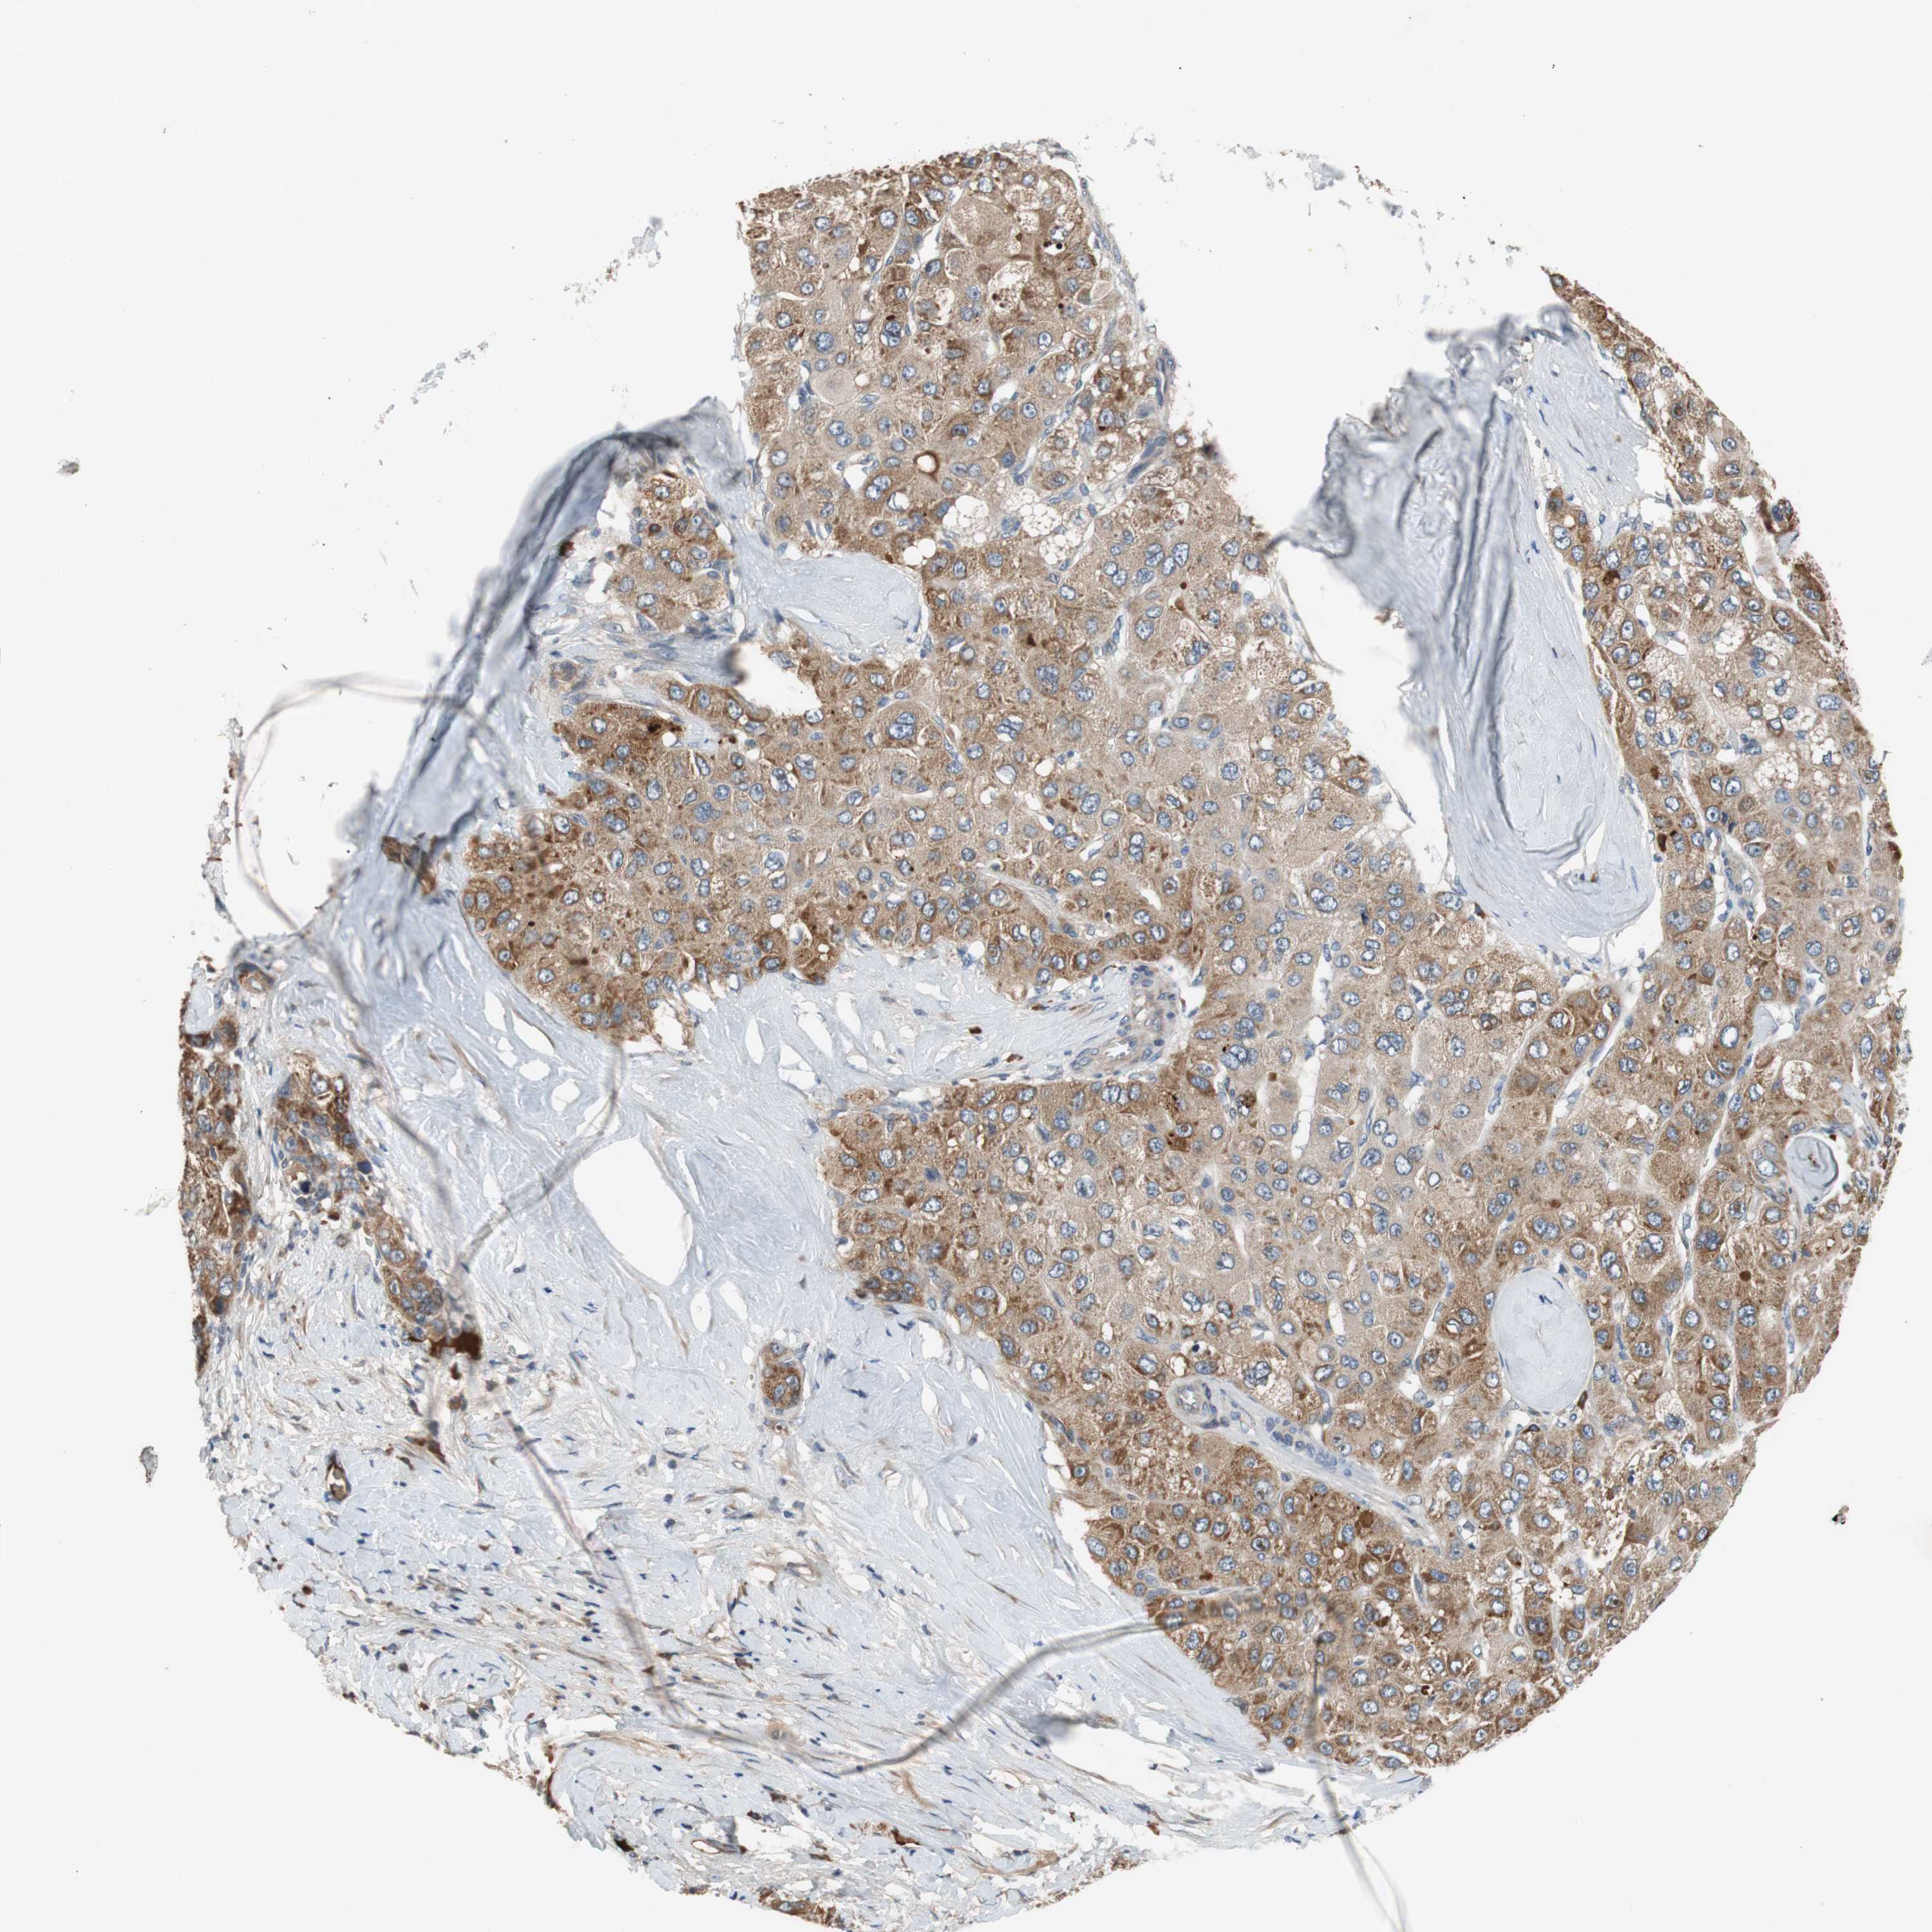

LIVER CANCER - Protein expressioni

A mouse-over function shows sample information and annotation data. Click on an image to view it in a full screen mode. Samples can be filtered based on level of antibody staining by selecting one or several of the following categories: high, medium, low and not detected. The assay and annotation is described here.

Note that samples used for immunohistochemistry by the Human Protein Atlas do not correspond to samples in the TCGA dataset.

Antibody stainingi

Antibody staining in the annotated cell types in the current human tissue is reported as not detected, low, medium, or high, based on conventional immunohistochemistry profiling in selected tissues. This score is based on the combination of the staining intensity and fraction of stained cells.

Each image is clickable and will lead to virtual microscopy that enables deeper exploration of all samples and also displays staining intensity scores, fraction scores and subcellular localization as well as patient and tissue information for each sample.

HPA046356

HPA048287

HPA050103

CAB009811

CAB032603

Cholangiocarcinoma

Carcinoma, Hepatocellular, NOS